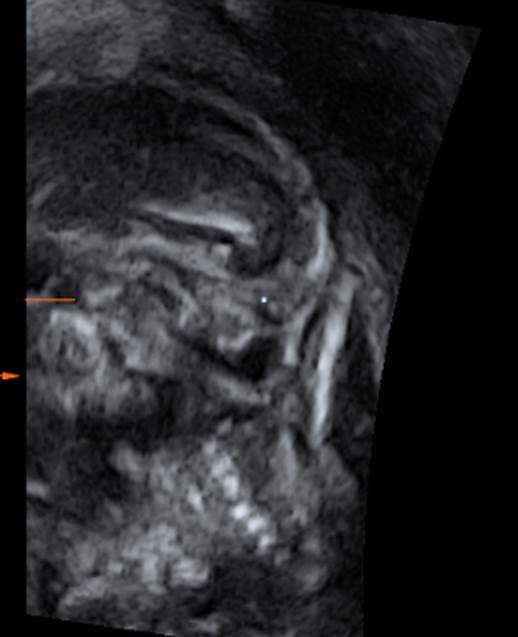

Вопрос 7

- Какая патология представлена на снимках?

- Специфическими признаки чего могут быть эти проявления?